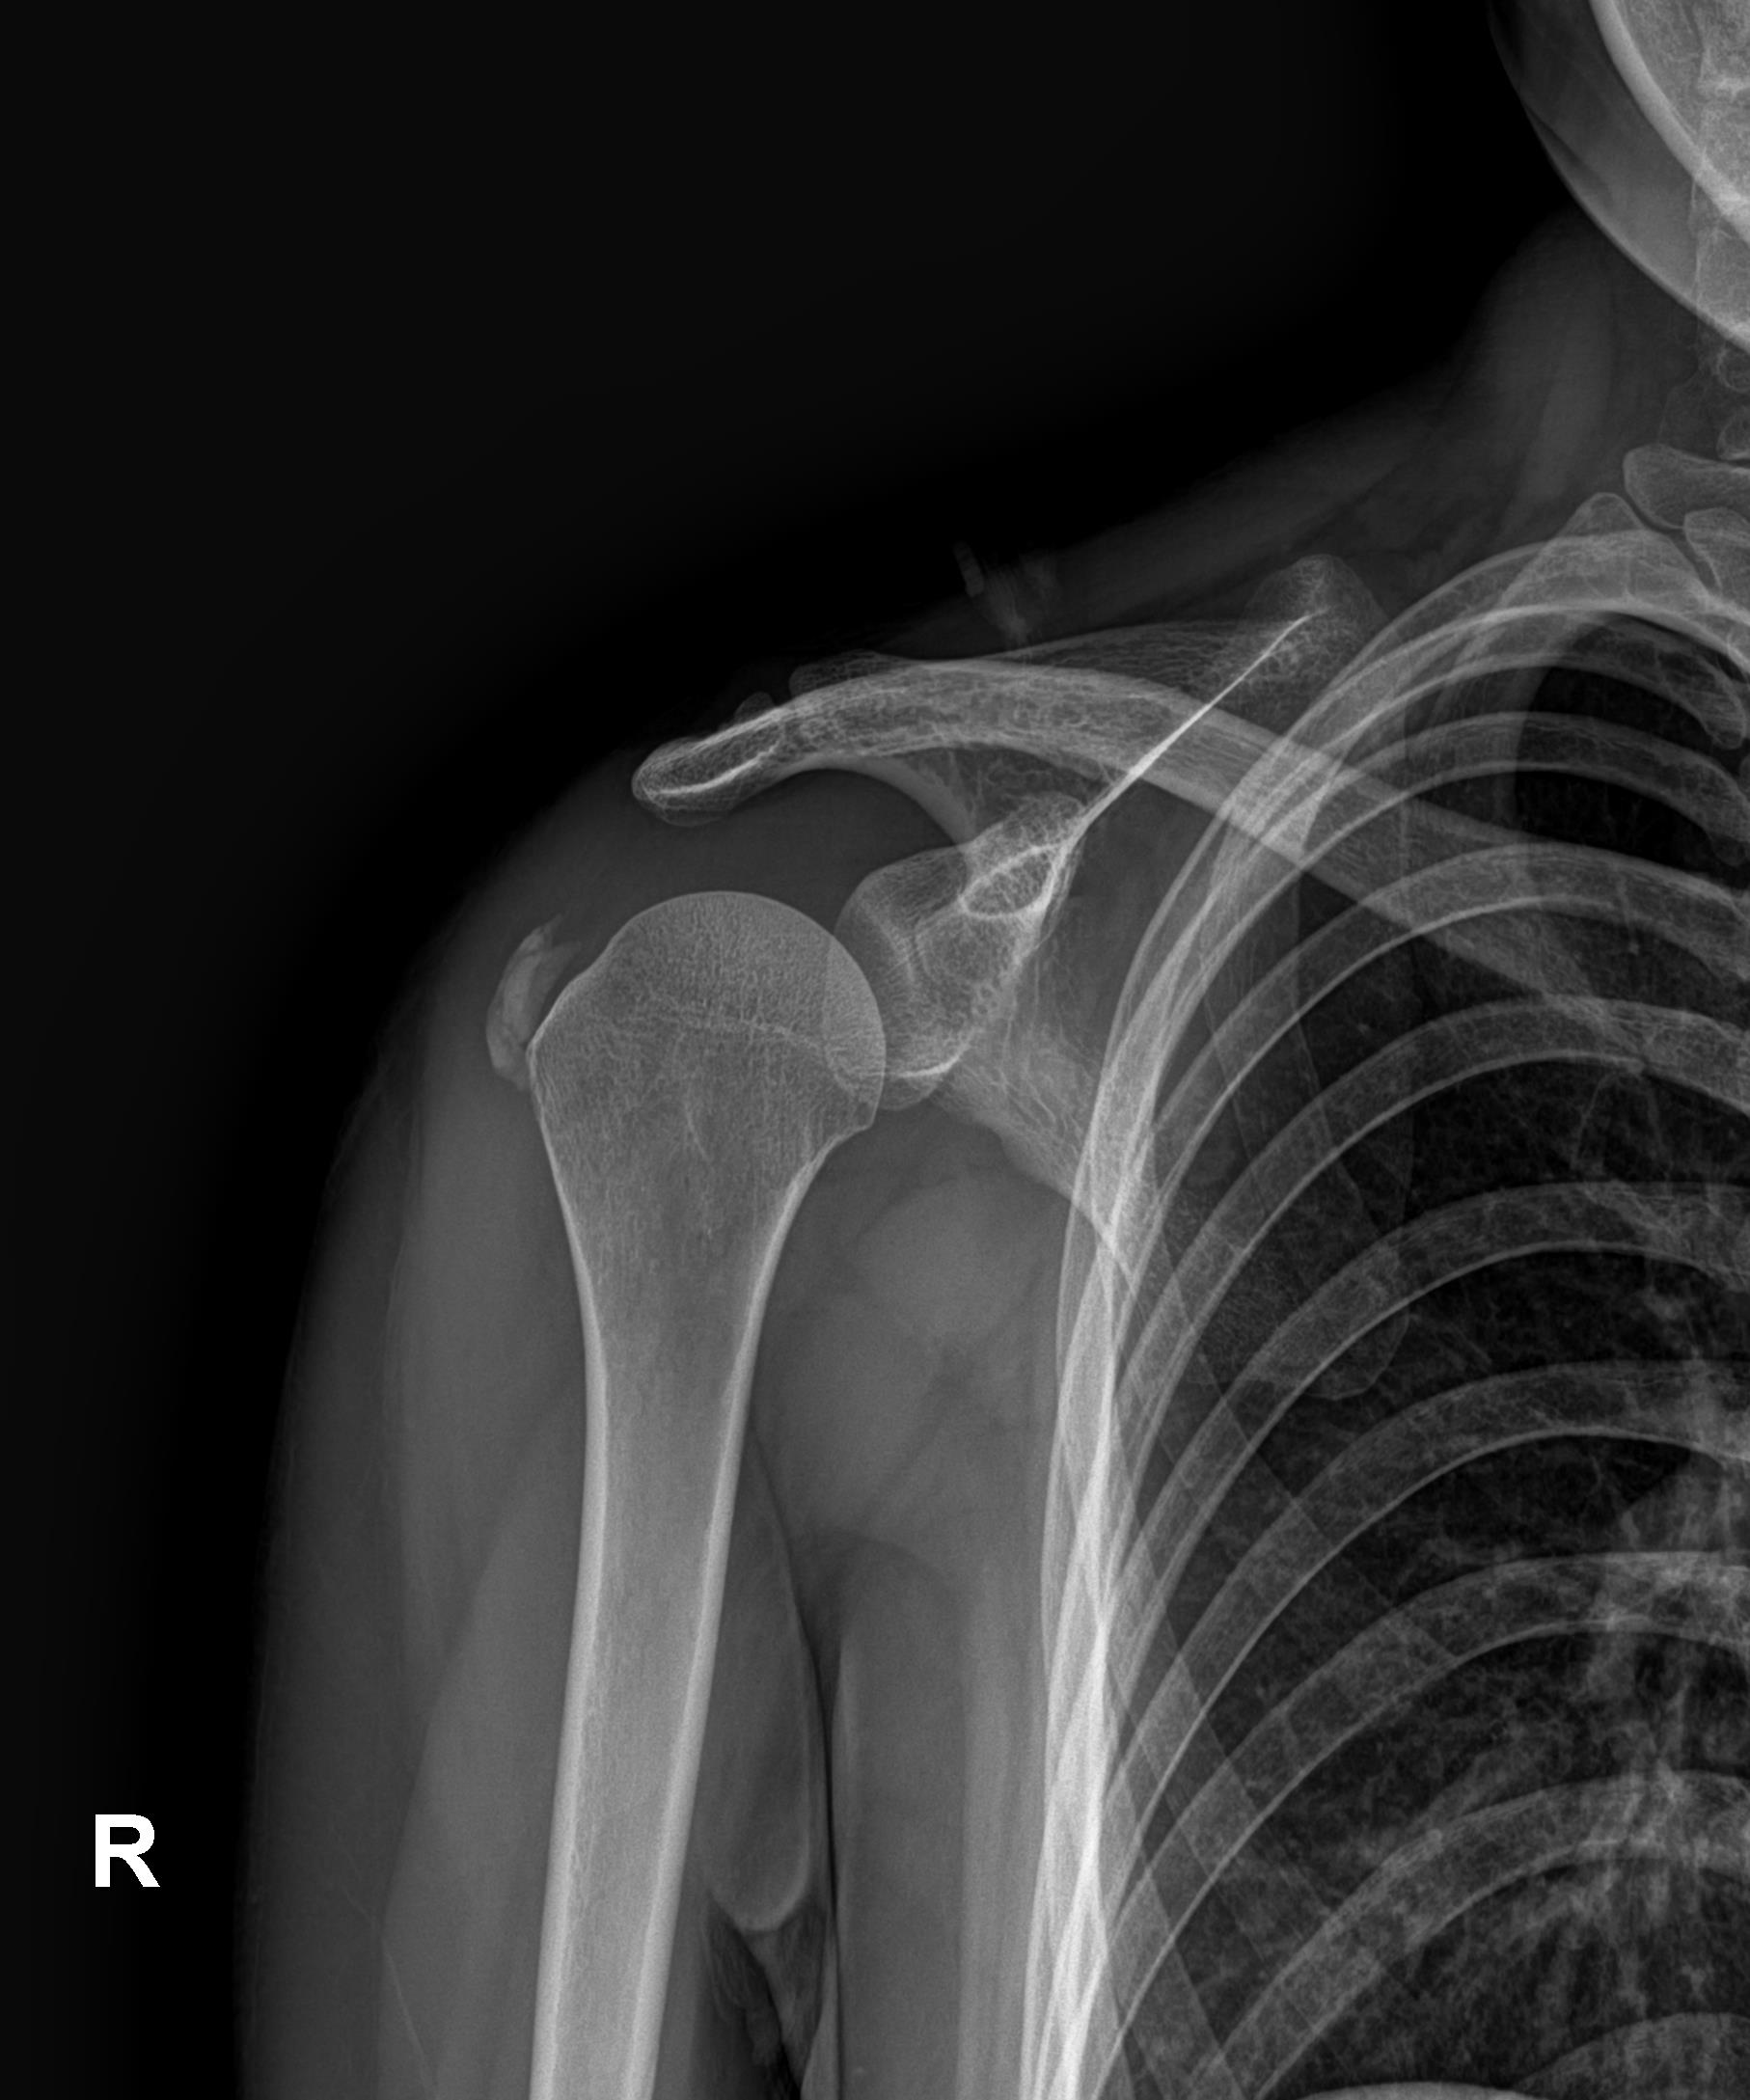

플래티넘에서의 치료

진단:

X-ray: 약 1.3cm 석회 (휴지기)

초음파: 석회 주변 인대 염증 소견

시술:

상완신경총 차단 마취

석회분쇄흡입술 시행

시술 시간: 35분

결과:

시술 직후 X-ray에서 석회 완전 제거 확인

기존 인대 염증은 재생주사로 추가 치료